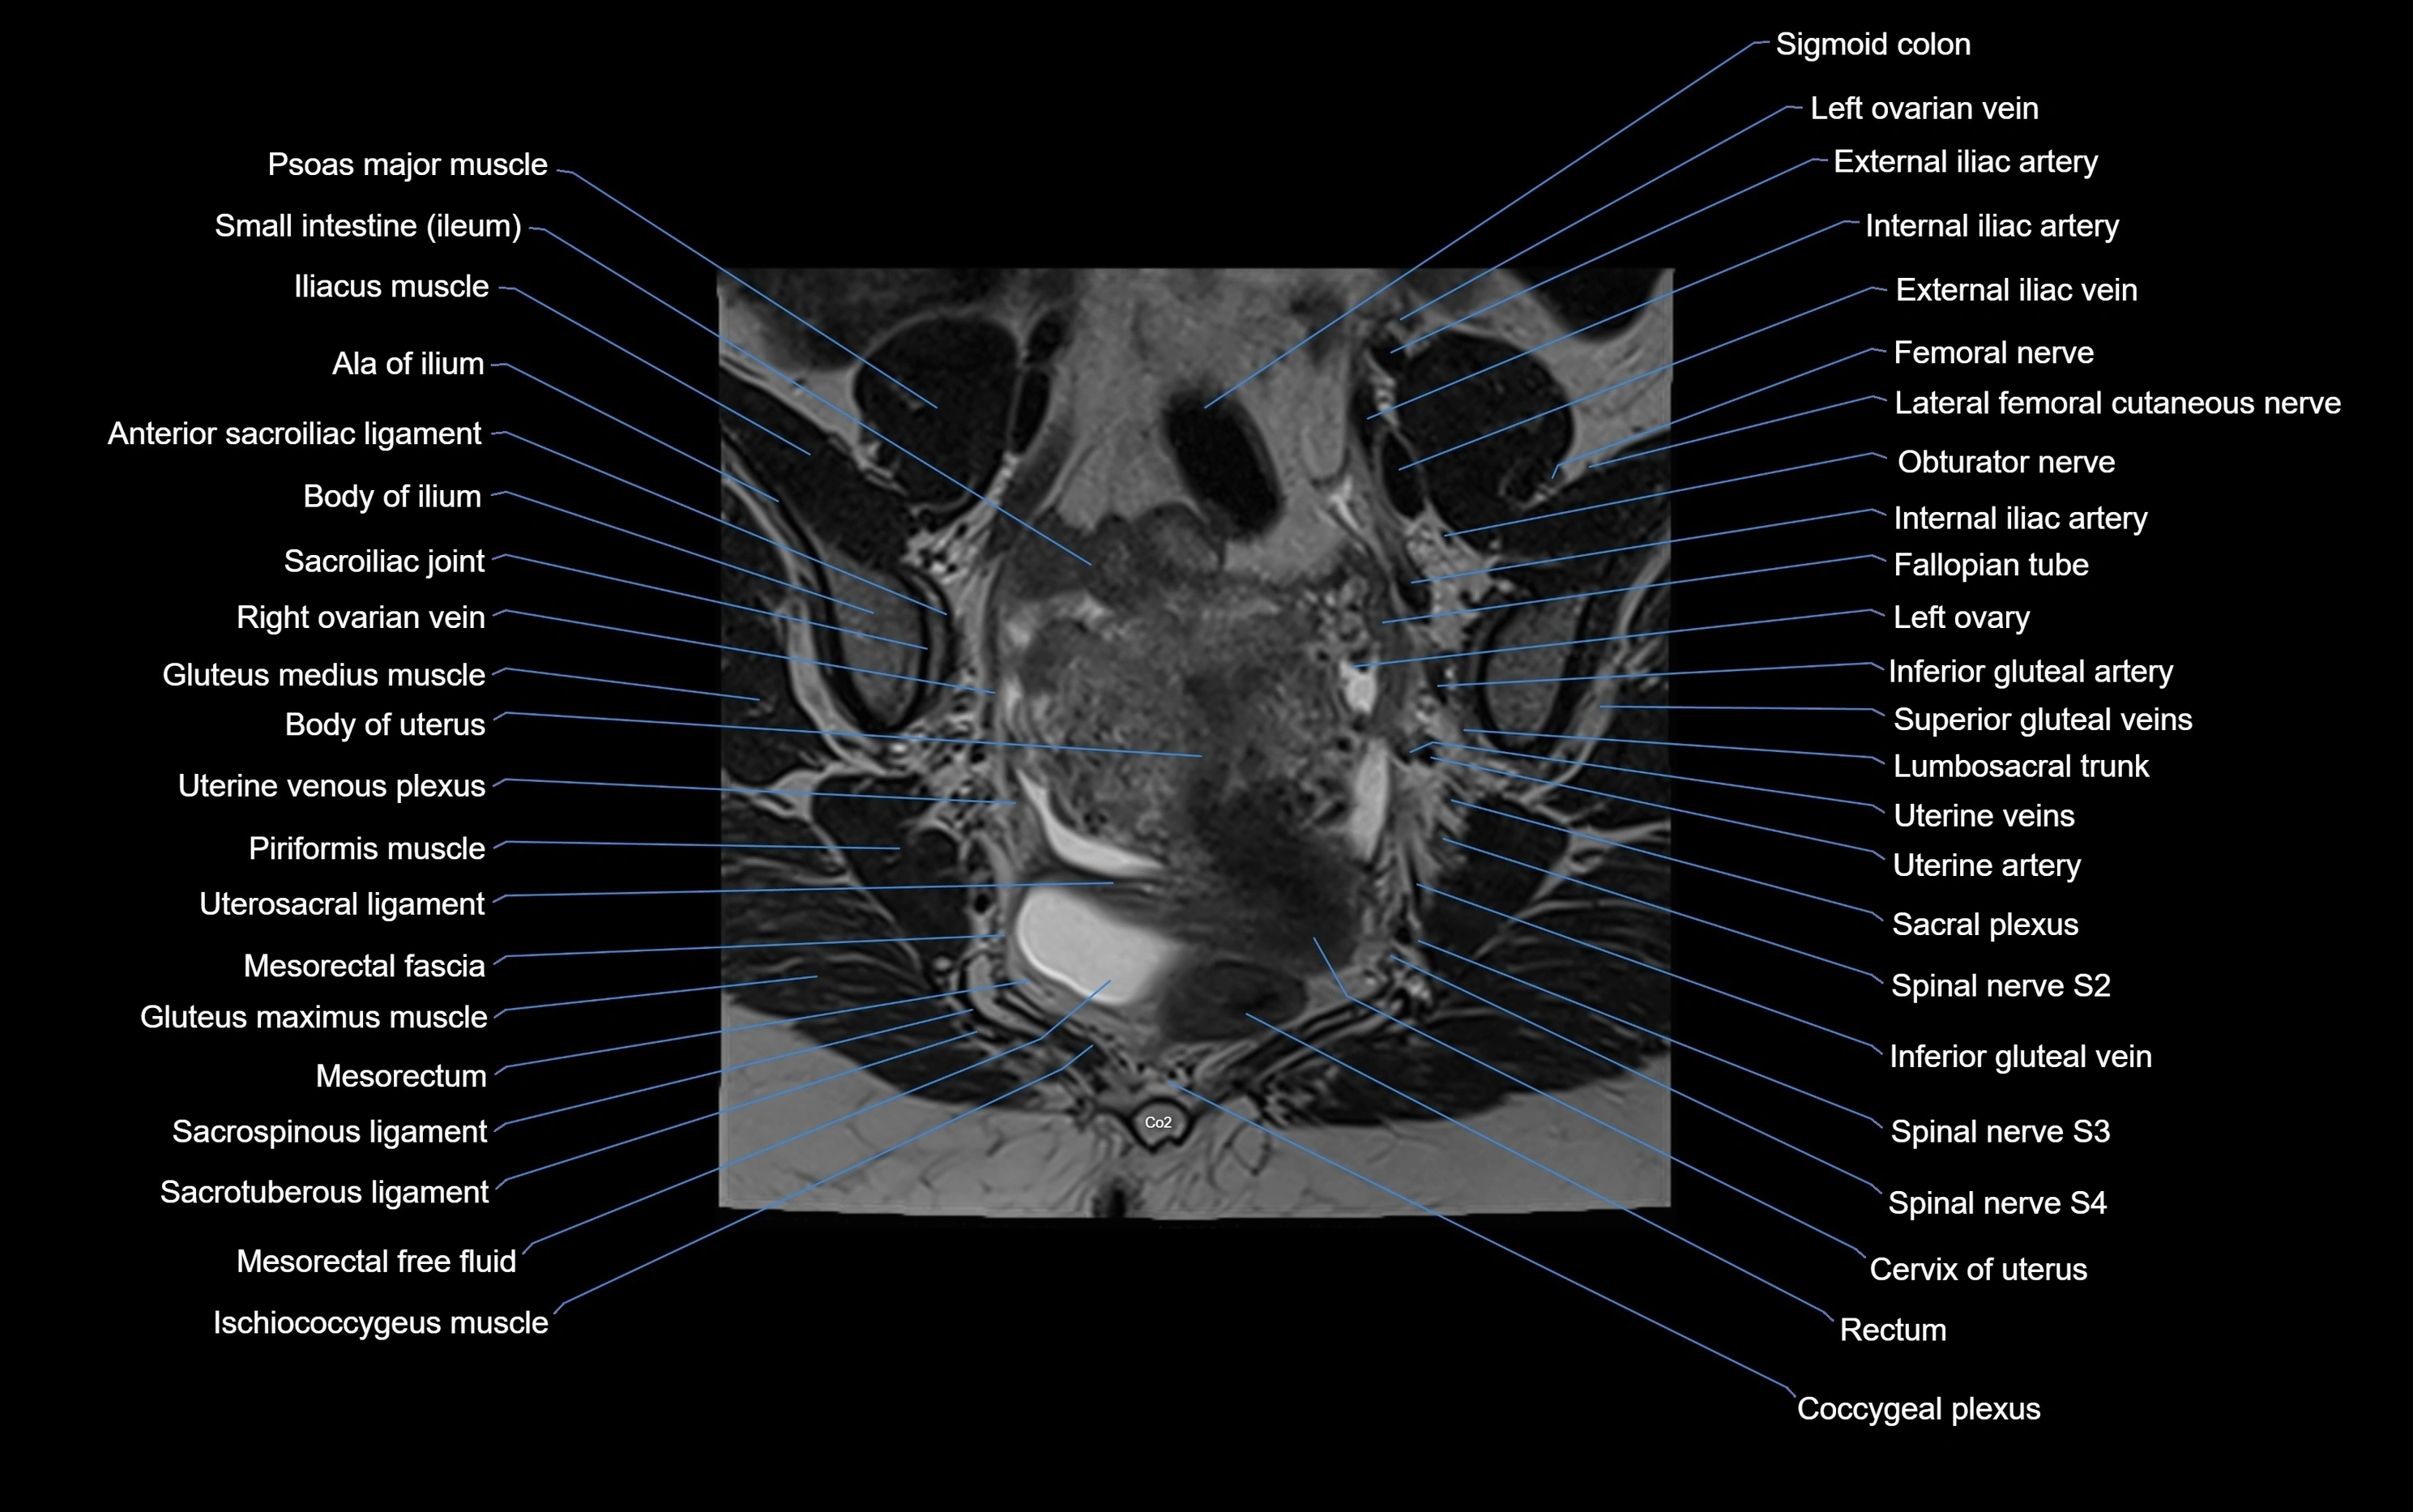

MRI Appearance

T1-weighted images:

• Cortical bone appears very low signal (dark); marrow shows intermediate signal

• Iliac fossa fat is bright against low-signal cortex

T2-weighted images:

• Cortical bone remains dark

• Marrow signal varies depending on fat content; edema or tumor shows hyperintensity

MRI image

image